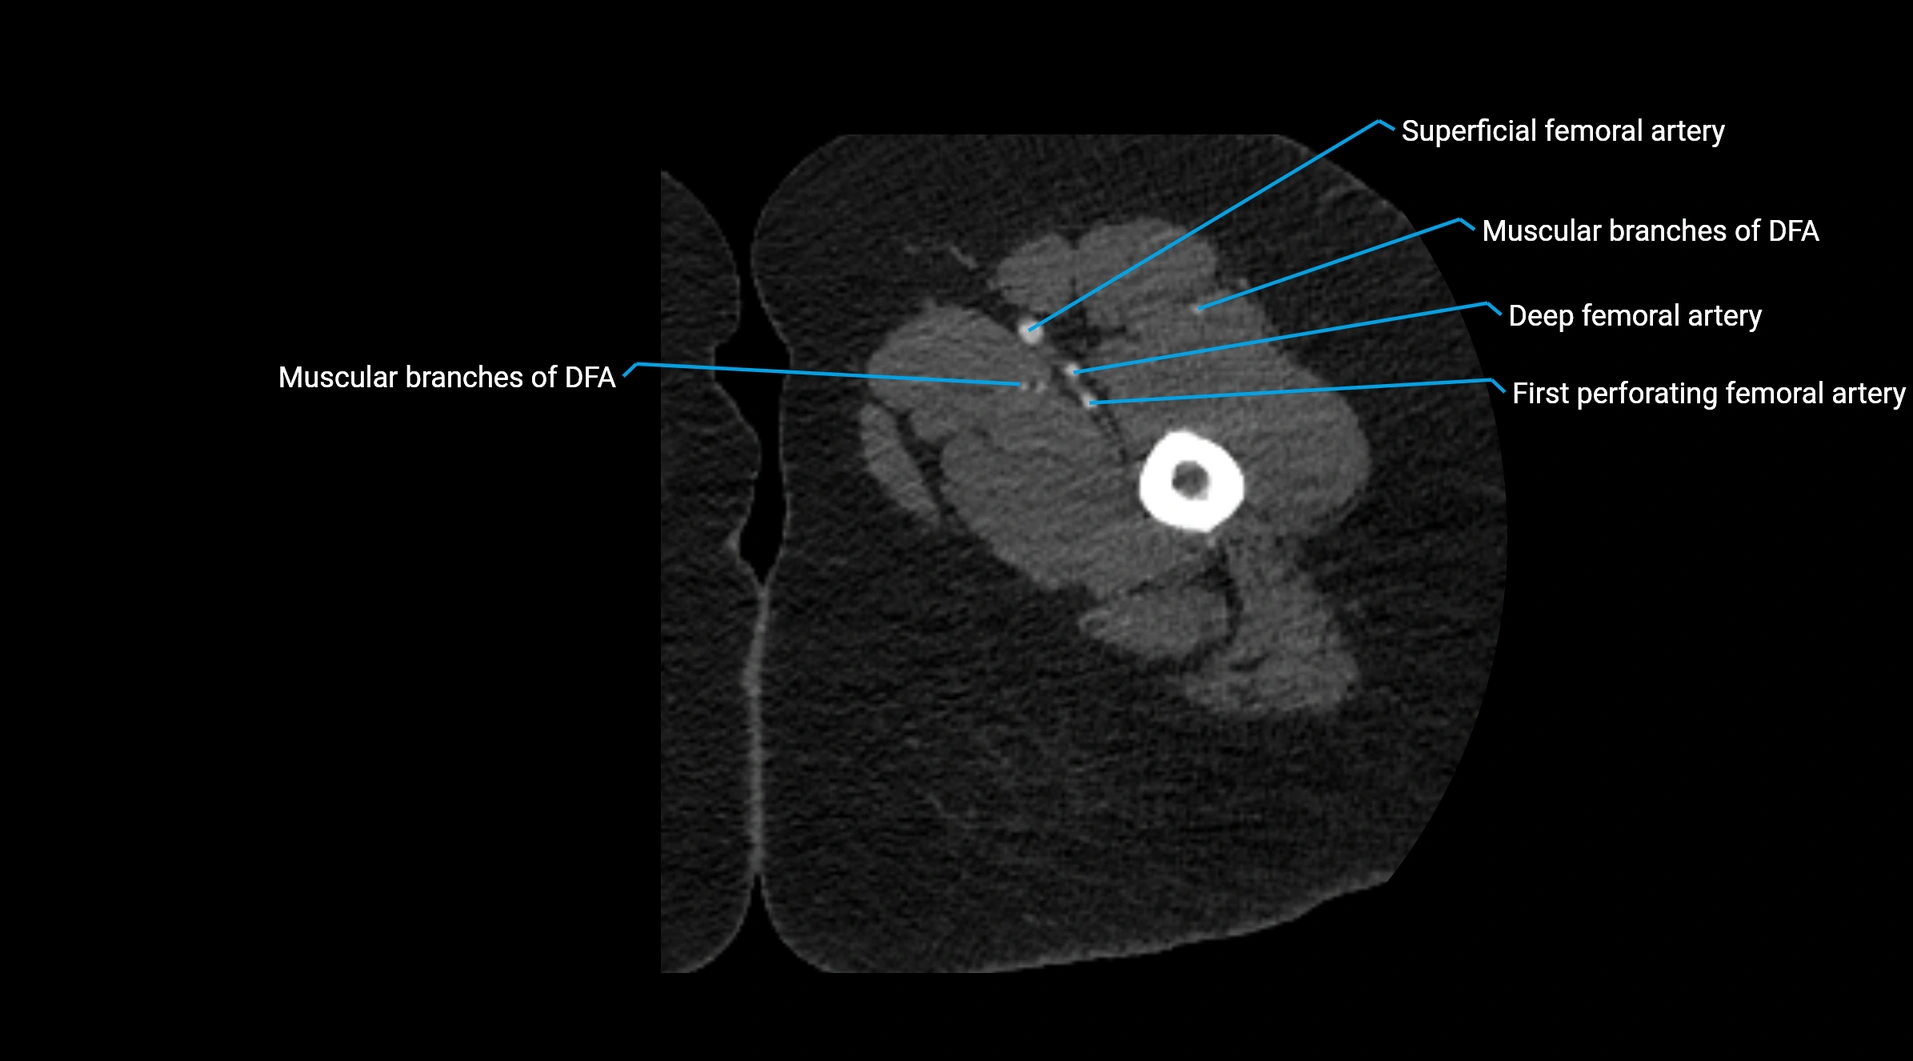

Contrast-enhanced CT (CTA):

• Gold standard for abdominal aortic imaging

• Provides excellent detail of lumen, wall, aneurysm, thrombus, and branch vessels

• Multiplanar and 3D reconstructions help in aneurysm measurement, stent graft planning, and dissection evaluation